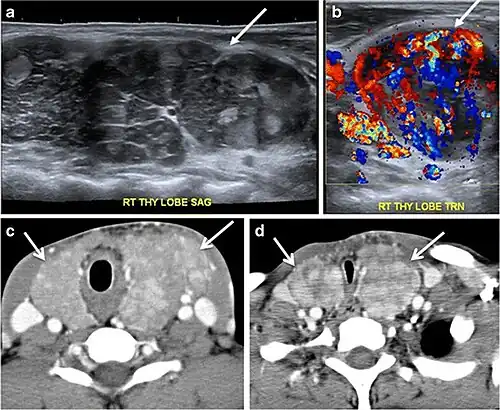

Fig. 14. A 19-year-old male patient known to have multi-nodular goiter and FNA, showing underlying Hashimoto's thyroiditis. a, b Sagittal and transverse greyscale and colour Doppler ultrasound of the neck demonstrate a hypoechoic enlarged right thyroid lobe with small hyperechoic regenerative nodules and marked hypervascularity (white arrows). c, d Enhanced axial CT scan images of the neck demonstrate a heterogeneously enhancing and enlarged thyroid gland, left more than right lobe, and the trachea is markedly narrowed.[1] -

Malignancy can coexist within the goiter and a CT scan may give a clue if there are abnormal cervical lymph nodes and/or signs of invasion. Retrosternal extension (Fig. 15) could affect the surgical approach, as a lower extent may require a partial or total sternotomy to facilitate complete resection. Therefore, the distance of the retrosternal extent from the sternal notch should be measured on a sagittal image.[1]

The interpreting radiologist should describe the mass effect, detailing its degree and direction of displacement of central structures, including the trachea, oesophagus, larynx, and pharynx. Attention should be directed to the upper extent of the goiter and structures immediately surrounding the thyroid gland, including the neuro-vascular structures, retropharyngeal space, and pre-vertebral space. The reporting radiologist should evaluate the vocal cords for symmetry and signs of vocal cord palsy.[1]